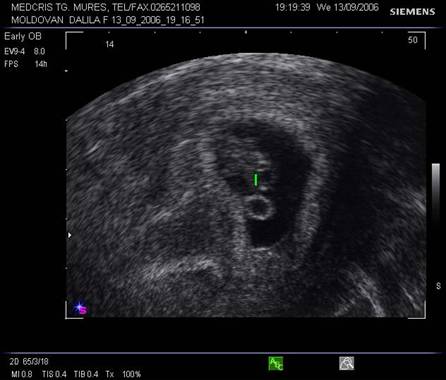

Fig nr.9. Vezicula vitelina, marcata cu sageata, la ecografia transvaginala, sarcina 5 sapt.